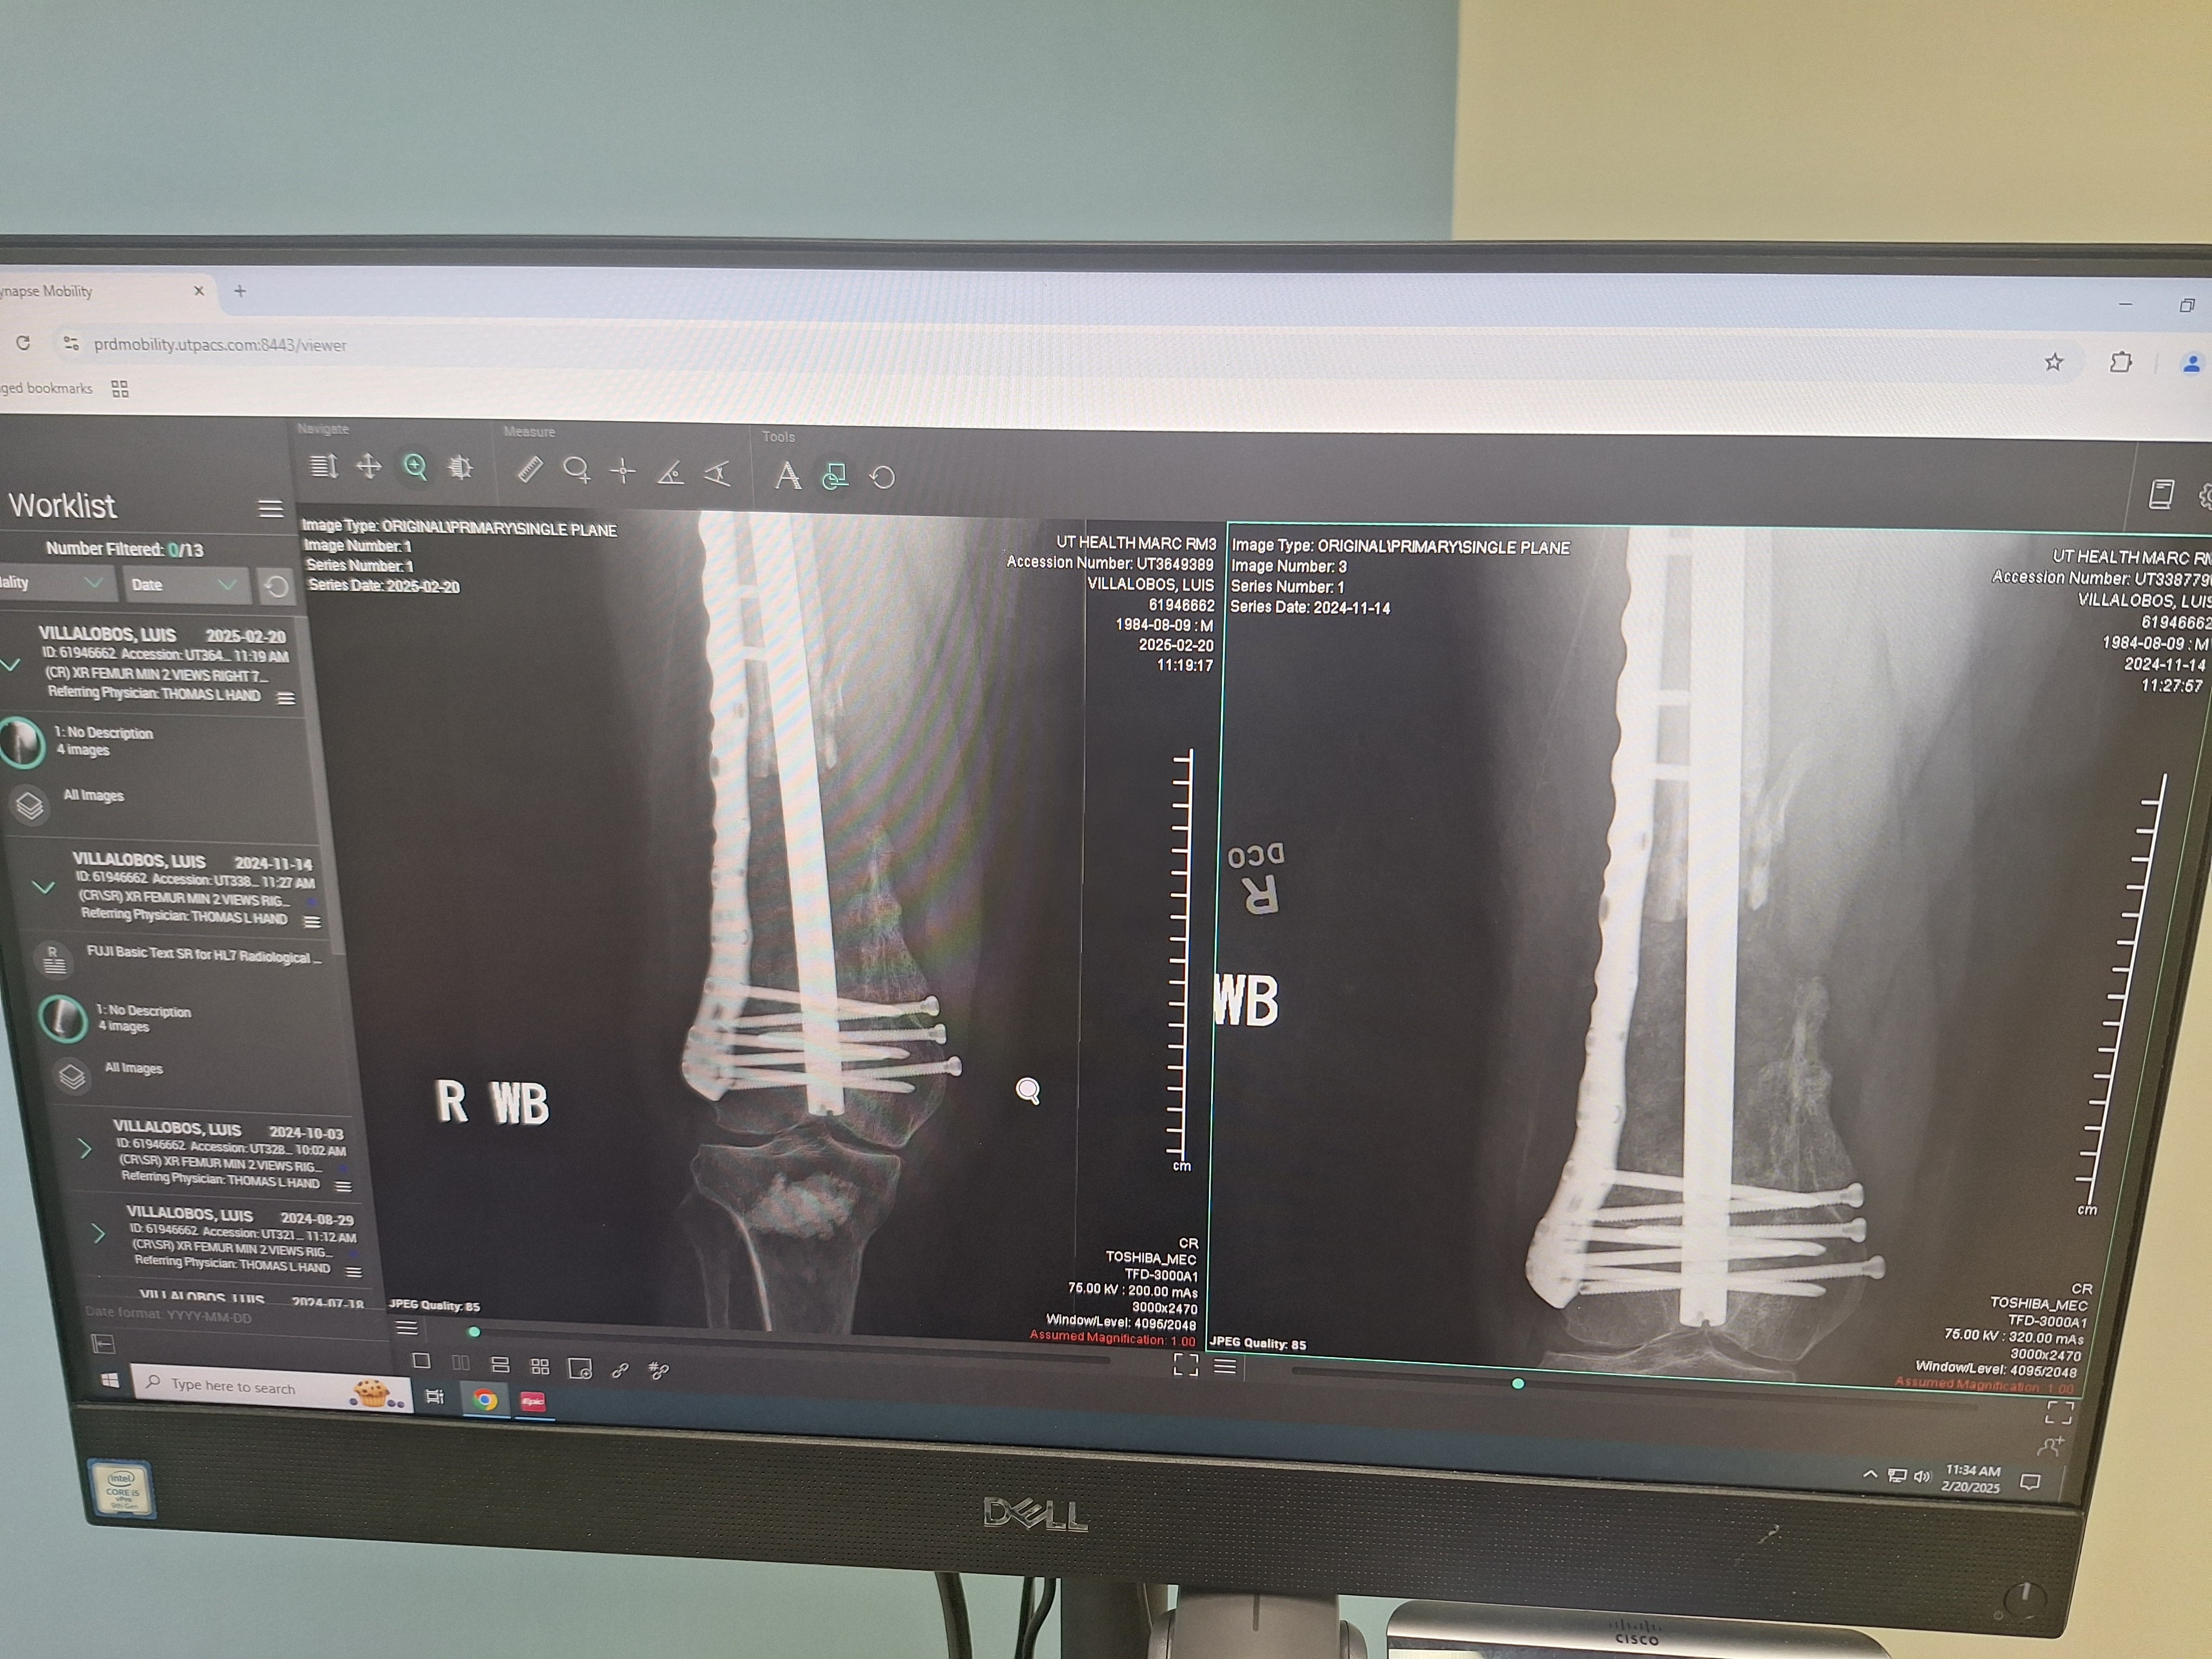

Hello everyone, my name is Luis, and I'm reaching out to you from a place of deep humility and urgent need. My life took an unexpected turn a couple of years ago when I was involved in a severe car accident that resulted in an open femur fracture.

After three incredibly challenging surgeries, it seemed I was finally on the long road to recovery and walking again. However, just when I thought I was turning a corner, a recent and severe internal infection struck, setting me back significantly. This infection has led to even more painful surgeries and has left me unable to bear weight or work.

To help you understand the extent of my medical journey, I've included a picture of my discharge paperwork, which reflects the severity and ongoing nature of my condition.

Mi nombre es Luis, y me dirijo a ustedes desde un lugar de profunda humildad y extrema necesidad. Mi vida dio un giro inesperado hace un par de años cuando sufrí un grave accidente automovilístico que resultó en una fractura abierta de fémur.

Después de tres cirugías increíblemente desafiantes, parecía que finalmente estaba en el largo camino hacia la recuperación y que volvería a caminar. Sin embargo, justo cuando pensaba que estaba superando lo peor, una infección interna reciente y grave me golpeó, lo que me ha retrasado significativamente. Esta infección ha provocado aún más cirugías dolorosas y me ha dejado incapaz de apoyar el peso de mi cuerpo o de trabajar.

Para ayudarles a comprender la magnitud de mi viaje médico, he incluido una foto de mi informe de alta hospitalaria, que refleja la gravedad y la naturaleza continua de mi condición.